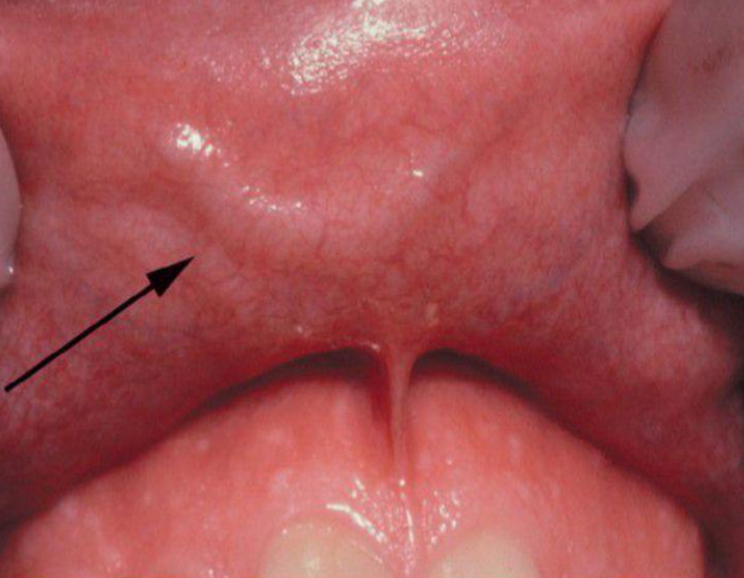

caliber persistent artery

upper lip vascular anomaly, BLEEDING RISK